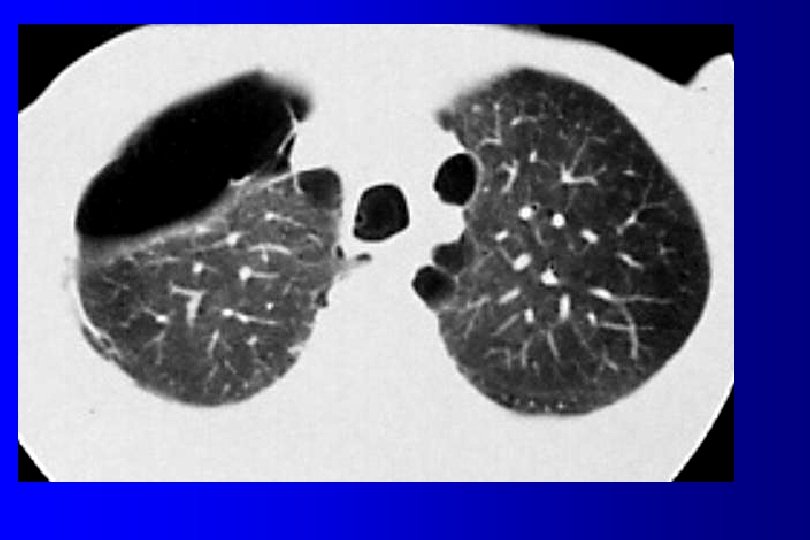

PLEUMOTHORAX imagerie üRadios standard (inspiration et en expiration forcée en cas de doute): hyperclarté entre la paroi et le parenchyme üTomodensitométrie (scanner recherche de bulles)